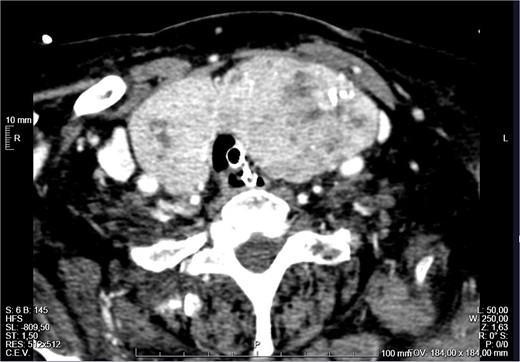

The patient was admitted to the Intensive Care Unit (ICU). A positive Pemberton sign was found on physical examination (Fig. 3). The thyroid hormones were normal with a slightly decreased TSH. The case was discussed in a multidisciplinary meeting and surgical treatment was decided. On the fourth day of admission, the patient underwent a total thyroidectomy (Fig. 4), parathyroid autotransplantation, and tracheostomy. The procedure was uneventful. The histological examination revealed nodular hyperplasia of the thyroid with foci of micropapillary carcinoma (4 mm) in the right lobe. The patient was extubated and discharged from the ICU on the second postoperative day. She initiated a physical and speech therapy programme. The follow-up nasopharyngoscopies showed a slow but progressive improvement of the laryngeal oedema, which required a longer admission. After a few unsuccessful attempts, she was finally decannulated on the 39th postoperative day and was soon discharged home. She progressed well and two and a half years after the surgery she is asymptomatic, with no dysphonia or respiratory distress. She has a subclinical hyperthyroidism that has been monitored in annual follow-up appointments.